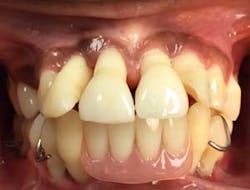

Six months postsurgery, a recommendation was made to the patient to remove the lower incisor teeth—Nos. 23, 24, 25, and 26—due to increased mobility and discomfort upon chewing. A lower anterior temporary partial was provided (figure 3).